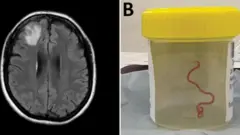

Австралиялык аялдын мээсинен 8 см. мите курт чыкты